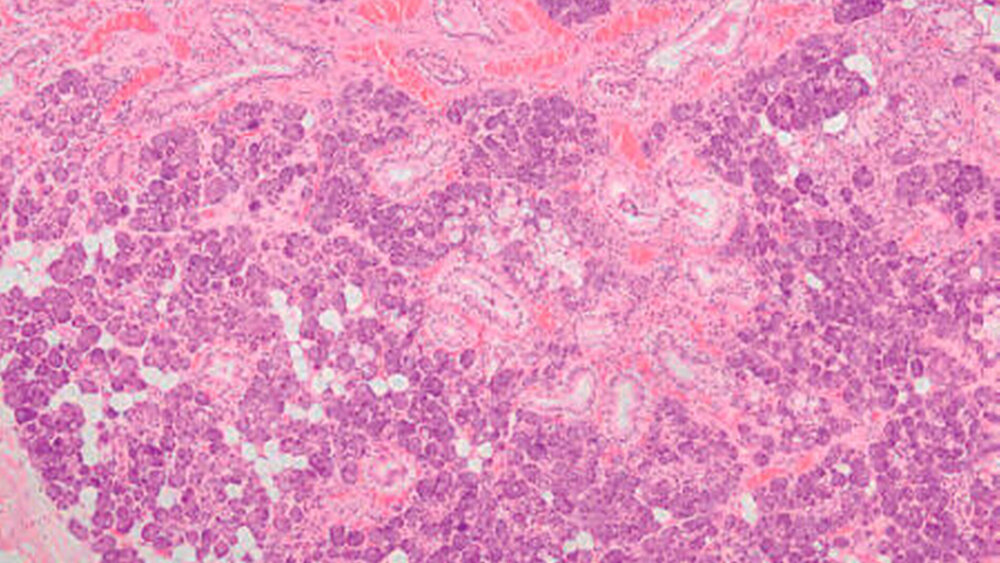

Die histopathologische Aufbereitung ergab neben seromukösem Speicheldrüsengewebe der Glandula sublingualis eine leicht chronisch fibrosierende und gering floride Sialadenitis (Abbildung 4).

Die histologische Aufbereitung bestätigt die bindegewebige Auskleidung der Ranulae gegenüber der epithelialen Auskleidung anderer Zysten, wie zum Beispiel einer Speichelretentionszyste.